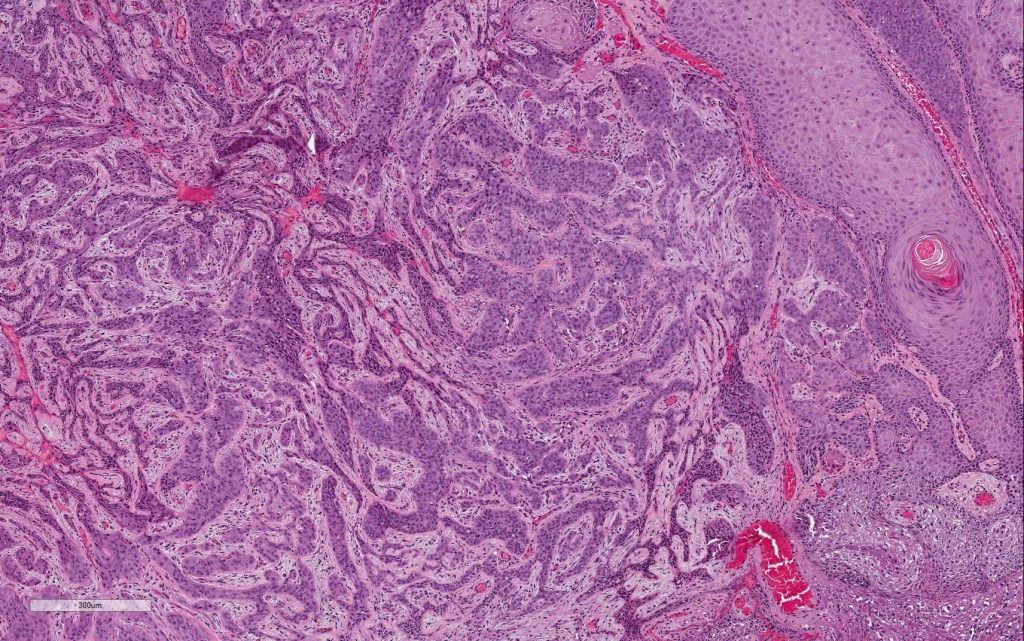

Histological features

•In situ (malignant hidroacanthoma simplex)

•Continuity/origin from epidermis (arises from the acrosyringium, distinguishes this tumor from hidradenocarcinoma)

•Pushing or infiltrating deep margin

•Broad anastomosing epithelial trabeculae